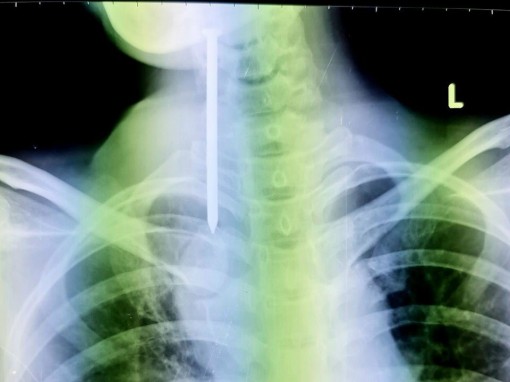

Cứu kịp thời bệnh nhân nuốt đinh

(CTO) - Khuya 28-9, người nhà đưa nam thanh niên mắc bệnh tâm thần (37 tuổi, ở tỉnh Vĩnh Long) đi cấp cứu tại Bệnh viện Đa khoa TP Cần Thơ do bệnh nhân ho ra máu.